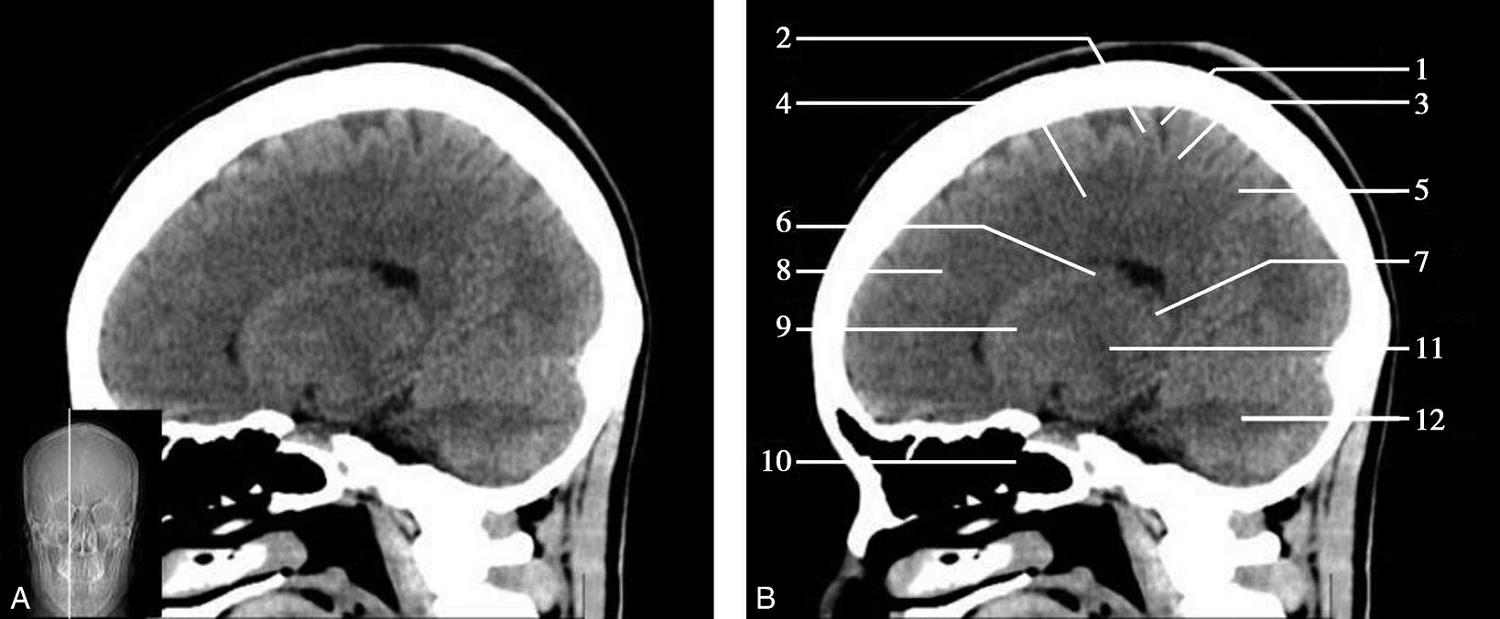

重要结构:胼胝体、垂体、中脑导水管、扣带回、中央沟、第三脑室、斜坡(图1-2-59、图1-2-60)。

图1-2-59 正中矢状面CT

A.矢状面;B.矢状面标注

1.中央沟;2.扣带回;3.胼胝体体部;4.侧脑室;5.中脑;6.胼胝体膝部;7.穹隆;8.第三脑室;9.胼胝体压部;10.垂体;11.中脑导水管;12.第四脑室;13.脑桥;14.蝶窦;15.斜坡;16.小脑扁桃体;17.延髓

图1-2-60 正中矢状面骨窗CT

1.顶骨;2.枕骨;3.斜坡;4.额骨;5.蝶鞍

此层面可显示胼胝体全貌,它位于层面中央区域,是呈上凸下凹的弧形结构,由前向后分为嘴、膝、体和压四部分。扣带回环绕胼胝体上方,扣带沟位于扣带回的上方。大脑半球中部和后部分别可见较深且恒定的中央沟和顶枕沟。中央沟为是额叶顶叶分界标志。

胼胝体下方为侧脑室及穹窿,第三脑室借穹窿与前上方的侧脑室体部分开,背侧丘脑的内侧面以及中脑顶盖分别为第三脑室的外侧壁和底。第三脑室向前籍室间孔与侧脑室相通,向下经中脑导水管通第四脑室。中脑腔狭窄呈管状,即称为中脑导水管,中脑导水管畸形,常见者为导水管的分叉畸形和狭窄,其次可见中脑导水管膈膜,造成先天性脑积水。

脑干由中脑、脑桥和延髓组成,自第三脑室底向下后稍斜行,移行于颈髓。由上至下,脑干腹侧可见脚间池、桥前池和延髓池,脑干背侧可见大脑大静脉池、四叠体池和小脑延髓池。

垂体位于蝶鞍内,其前部为腺垂体,后上部分为神经垂体。垂体下方为鞍底及蝶窦,上缘因鞍膈存在而平直,垂体借垂体柄向上连于丘脑下部。垂体的前上方见视交叉和视束。斜坡作为前颅窝底的重要组成部分与多个重要结构相比邻,矢状位呈三角形,颅内肿瘤或颅外鼻咽部恶性肿瘤均可侵犯至此,原发肿瘤常见为脊索瘤。小脑幕居枕叶和小脑之间,向后下连接窦汇,向前至中脑后方游离,称小脑幕切迹。小脑幕下方为小脑扁桃体。成年人小脑扁桃体下缘由枕骨大孔向下疝入椎管超过5mm称为Chiari畸形,以矢状位显示最佳。